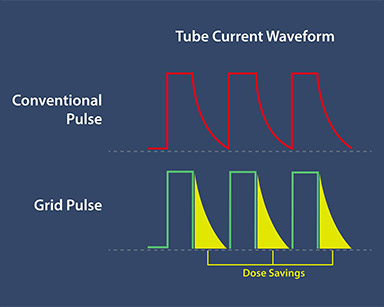

Режимы с изменяемой дозой, включая Grid Pulsed Fluoro

Ultimax-i предлагает 3 режима изменяемой дозы:

- непрерывный

- импульсный

- сеточный импульсный

Пользователи могут выбрать оптимальный режим дозы в зависимости от диагностических потребностей и особенностей пациента.